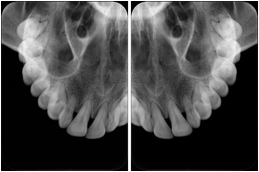

- OO-1. Intra-oral Full Mouth Series Structured Display